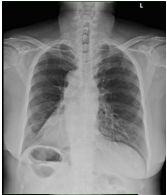

2. A 27-year-old woman had productive cough for one month.